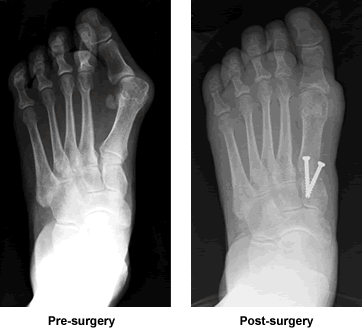

By the time I found my way to Dr. Leavitt's office in the spring of 2009, I had consulted with at least 6 podiatrists and orthopedic surgeons. A severe bunion on my left foot was worsening, pushing my other toes out of position. I had always rejected the idea of surgery because I didn't have severe pain in the joint. However, over the past 5 years, discomfort in different parts of the foot was increasing; I could no longer walk barefoot on a beach, and found it difficult to find reasonable shoes.

Dr. Leavitt took a thoughtful, realistic approach in helping me consider the pros and cons of undergoing elective reconstructive surgery to correct these problems. He took into consideration not just my age (69 at the time) but my level of fitness and activity, as this would determine how well I could manage the post-surgery regimen. I understood that mine was a "severe" case and that it would not be a simple surgery. The short-term picture - almost two months on crutches - seemed daunting. Discussing the details of my case with Dr. Leavitt was extremely helpful; for the first time I felt as if I had sufficient information, and that I was in the hands of a highly experienced surgeon. I scheduled my surgery for late summer, a time when it would be convenient to take a 3- to 4-week leave from my work.

Now, five months post-surgery, I am wearing normal shoes and walking a mile to and from work as well as up 3 flights of stairs to my office. Last month, we traveled to Puerto Rico where I walked daily on the beach. Yesterday, I cross-country skied for 2 hours. Hopefully, this "good outcome" will be pertinent to others considering similar procedures.